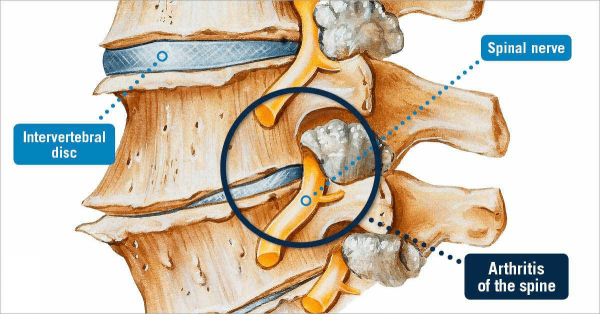

Spondylóza: Čo to vlastne znamená

Spondylóza je široký pojem, ktorý jednoducho označuje nejaký typ degenerácie chrbtice. Najčastejšie sa termín spondylóza používa na opis osteoartritídy chrbtice, ale bežne sa používa aj na opis… Viac

Čo je spinálna osteoartritída (artritída fazetového kĺbu)?

Väčšina ľudí trpí v určitom okamihu svojho života bolesťou krku alebo chrbta. Keď sa bolesť a stuhnutosť vyvíjajú postupne a stávajú sa chronickými, príčinou môže byť osteoartritída. Osteoartritída… Viac